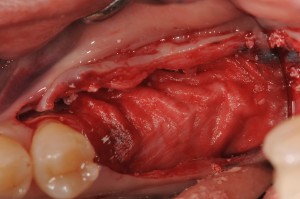

歯槽頂にGBRするために、インプラントは浅く埋入し、出血を促すためのデコルチケーションをしています。

Bi0-ossと自家骨を混和して、歯槽の形態を整えます。